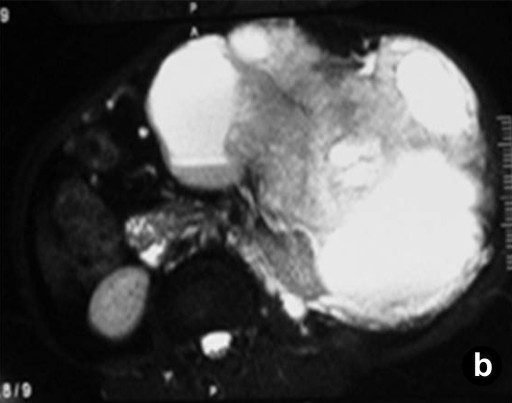

Routine laboratory investigations were within normal limits except for anemia (hemoglobin: 8 g/dL; reference range: 12-15 g/dL). A contrast-enhanced computerized tomogram of the abdomen (Figure 1) revealed a large heterogeneously enhancing mass of mixed echogenicity (mostly cystic with a few solid areas), measuring 35x30x25 cm, in the region of the body and the tail of the pancreas. The mass did not communicate with the main pancreatic duct. There were no ascites or lymphadenopathy. On magnetic resonance imaging, the mass was hypointense on T1-weighted imaging and hyperintense (cystic) on T2-weighted imaging with hemorrhagic and calcific foci (Figure 2). The possibility of a malignant cystic neoplasm of the pancreas was considered. Upper gastrointestinal endoscopy and colonoscopy showed no abnormalities. At laparotomy, a large mass was found to arise from the body and tail region of the pancreas. There was no attachment to the stomach, and the colon was stretched over the mass. There was no evidence of peritoneal dissemination. To achieve a R0 resection, a distal pancreatectomy, splenectomy and left hemicolectomy were performed.

Figure 2. Magnetic resonance imaging showing the mass to be hypointense on T1-weighted imaging (a.) and hyperintense on T2-weighted imaging (b.). |